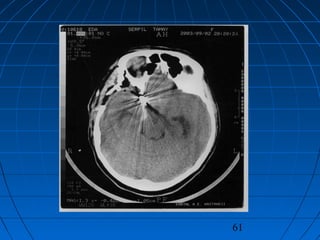

 ST: 43 yaşında kadın hastaST: 43 yaşında kadın hasta

 BaşağrısıBaşağrısı (akut şiddetli, birkaç saat(akut şiddetli, birkaç saat

içinde)içinde)

 GKS 13 (WFNS grade 2)GKS 13 (WFNS grade 2)

 Fisher grade IIIFisher grade III

CERRAHİCERRAHİ

 Sağ pterional trans-sylvian yaklaşımSağ pterional trans-sylvian yaklaşım

 Proksimal ICA Anevrizması kliplendiProksimal ICA Anevrizması kliplendi